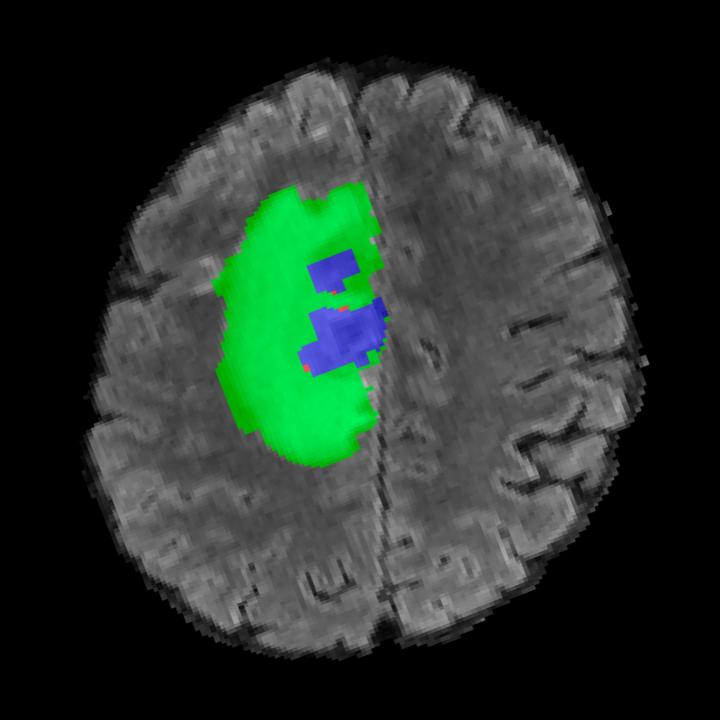

Tumour Information Preservation. For the brain tumor segmentation, we use a Swin UNETR model[27, 70], trained with random rotation, and intensity as data augmentation. In Figure 5, we highlight the tumor profiles of the generated MRIs compared to the ground truth tumour profile. In the test set with human ground-truth annotations (), the real MRI Dice score is 85.15 while the generated MRIs from a single slice have a dice score of 83.09. This shows how the generated MRIs indeed preserve the tumor information and can act as an affordable and informative pseudo-MRI, before conducting an actual costly MRI examination in hospitals.

B.4 Tumour Information Preservation

On the test set with human ground-truth annotations (), the brain volumes generated from single slice input preserve the volume of the different tumour components (paired t-test, for all 3 classes) (see Table 3). The real MRI Dice scores are put for reference to our generated MRIs. X-Diffusion outperforms baselines TPDM [36] and ScoreMRI [18] in tumour preservation (see Table 3 and Figure 12). We ran experiments comparing the tumour segmentation Dice Score varying X-Diffusion configurations. The multi-slice input X-Diffusion achieves a marginally better Dice Score than the single-slice input model (83.47 83.09). We also ran experiments with slice input used for volume reconstruction intersecting or not with tumour. We observe on average a drop of 6% Dice Score (see Table 3). Further away from the tumour the input slice for volume reconstruction is selected, and we observe a linear decrease in tumour segmentation Dice Score with the lowest value of 77.21 Dice Score (see Figure 15).